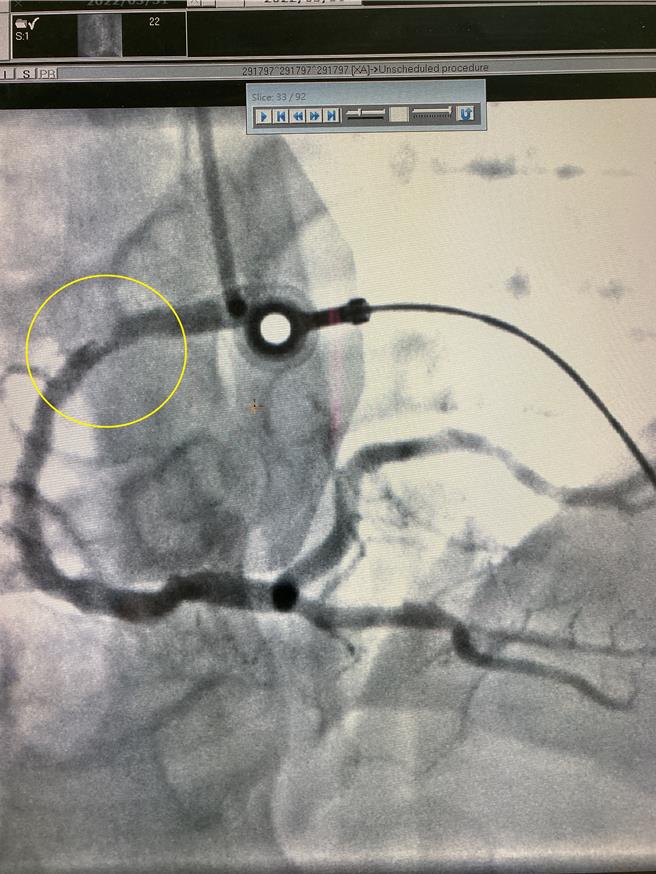

吴先生庆幸说,没想到自己骑机车突然被蜜蜂螫咬,意外引发心肌梗塞,右侧冠状动脉近端阻塞,紧急进行心导管手术,感谢同事硬将他送医,还有医院细心治疗,让自己从鬼门关被拉回人世间。其实他遭蜜蜂螫伤前,就出现易疲劳、易喘等心臟疾病的徵兆,决定戒菸、减重,让自己能尽快恢復健康。